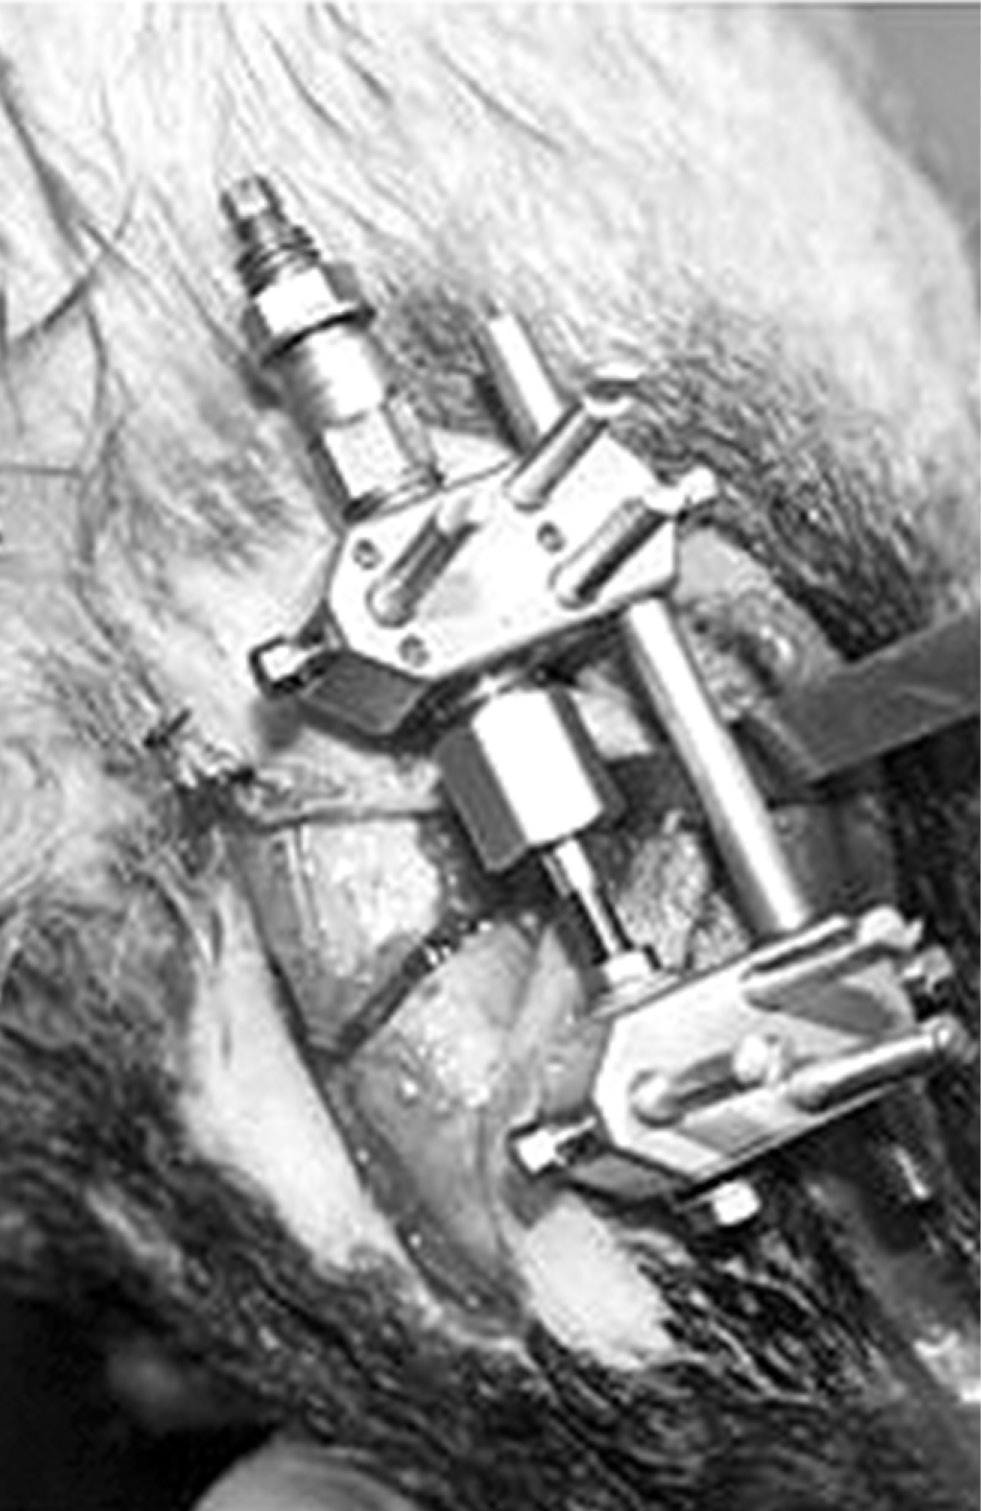

Были подобраны опытные животные (щенки) одного возраста и комплекции, которых разделили на группы. На базе ветеринарного центра в условиях общего внутривенного наркоза устанавливали дистракционные аппараты на тело нижней челюсти собак справа и слева (рис. 1) с одномоментным рентгенологическим контролем фиксации аппаратов и линии проведённой остеотомии. На шею каждой собаки фиксировали защитный пластиковый конус (воротник) для предотвращения повреждения аппаратов и комплекта электроники.

Рис. 1. Дистракционное устройство, зафиксированное на тело нижней челюсти собаки справа.

Fig. 1. The distraction device fixed on the lower jaw body of the dog on the right.